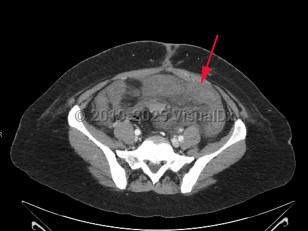

Mesenteric ischemia is relatively rare with an incidence of roughly 5-8 per 100 000 per year. The incidence of mesenteric ischemia increases significantly with age, with a median age at presentation of 67 years. While advancements in treatment strategies have made significant improvements in the mortality of mesenteric ischemia, it remains high at approximately 50%. As with overall incidence, mortality increases significantly with age.

Patient presentation is characterized by the sudden onset of severe abdominal pain with a benign abdominal examination, often referred to as "pain out of proportion to exam." Many patients will develop vomiting and diarrhea. Bloody diarrhea due to bowel necrosis is a late finding. In occlusive disease, symptoms progress rapidly over hours to days. Those with thrombotic disease may report weeks to months of preceding symptoms suggestive of chronic mesenteric ischemia. These can include abdominal pain worsened after eating (so-called "intestinal angina"), fear of eating, and weight loss. Nonocclusive mesenteric ischemia is often observed in the setting of critical illness. Worsening acidosis, hemodynamic instability, feeding intolerance, diarrhea, and abdominal distention are all worrisome signs.